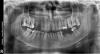

gosha.mi Опубликовано 4 июня, 2012 Поделиться Опубликовано 4 июня, 2012 (изменено) Здравствуйте! хочу поставить имплантаты вместо отсутствующих зубов. Что и как можно сделать? Какие могут возникнуть сложности? Изменено 4 июня, 2012 пользователем gosha.mi Ссылка на комментарий

Bier Опубликовано 4 июня, 2012 Поделиться Опубликовано 4 июня, 2012 сложности возникнут в связи со значительным выдвижением зубов антагонистов в зону дефекта. Ссылка на комментарий

Bier Опубликовано 4 июня, 2012 Поделиться Опубликовано 4 июня, 2012 Это в обоих местах? И какие в этом случае могут быть варианты действий ,кроме спиливания антагонистов? А так же ,нужен ли в моем случае синус-лифтинг? в обоих местах. Можно попробовать их затолкать обратно.Синуслифтинг скорее всего не нужен. Но много чего нужно пролечить до имплантации. Ссылка на комментарий

Dr. Surkin Опубликовано 6 июня, 2012 Поделиться Опубликовано 6 июня, 2012 Удалять 18, 17, 28.Лечить кариес 17, 47, 34Эндолечение 24, 25, 26Искусственные коронки на 16, 24,25,26, 34 Это как минимум. Ссылка на комментарий